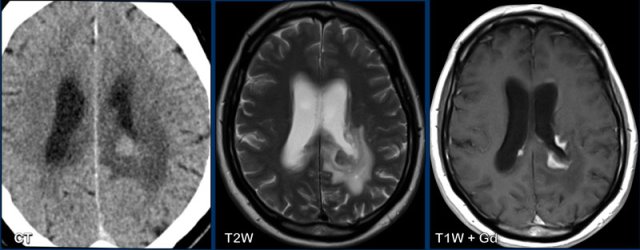

Lymphoma

These images are of a 63-year old patient.

Images

CT shows a dense periventricular

lesion with surrounding edema.

On the T2W-image the lesion has a relatively low density. There is homogeneous enhancement of the lesion with multiple periventricular enhancing

lesions.

The density on the CT and the distribution are highly suggestive of lymphoma.